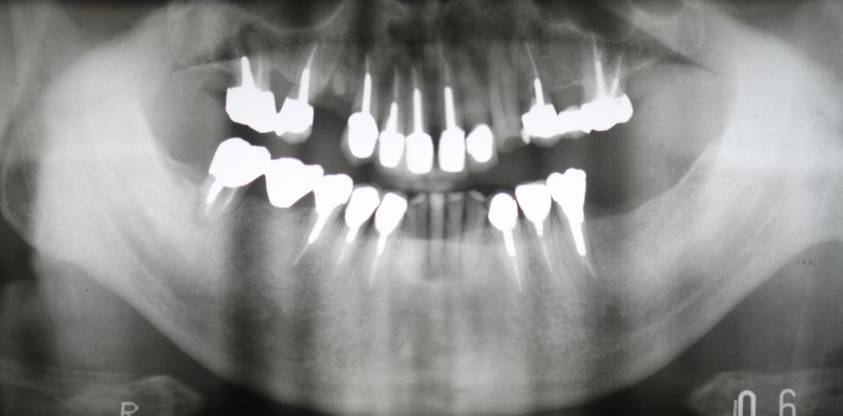

術前パノラマレントゲン写真。根の周りが黒くなり、骨がなくなっていることがわかります